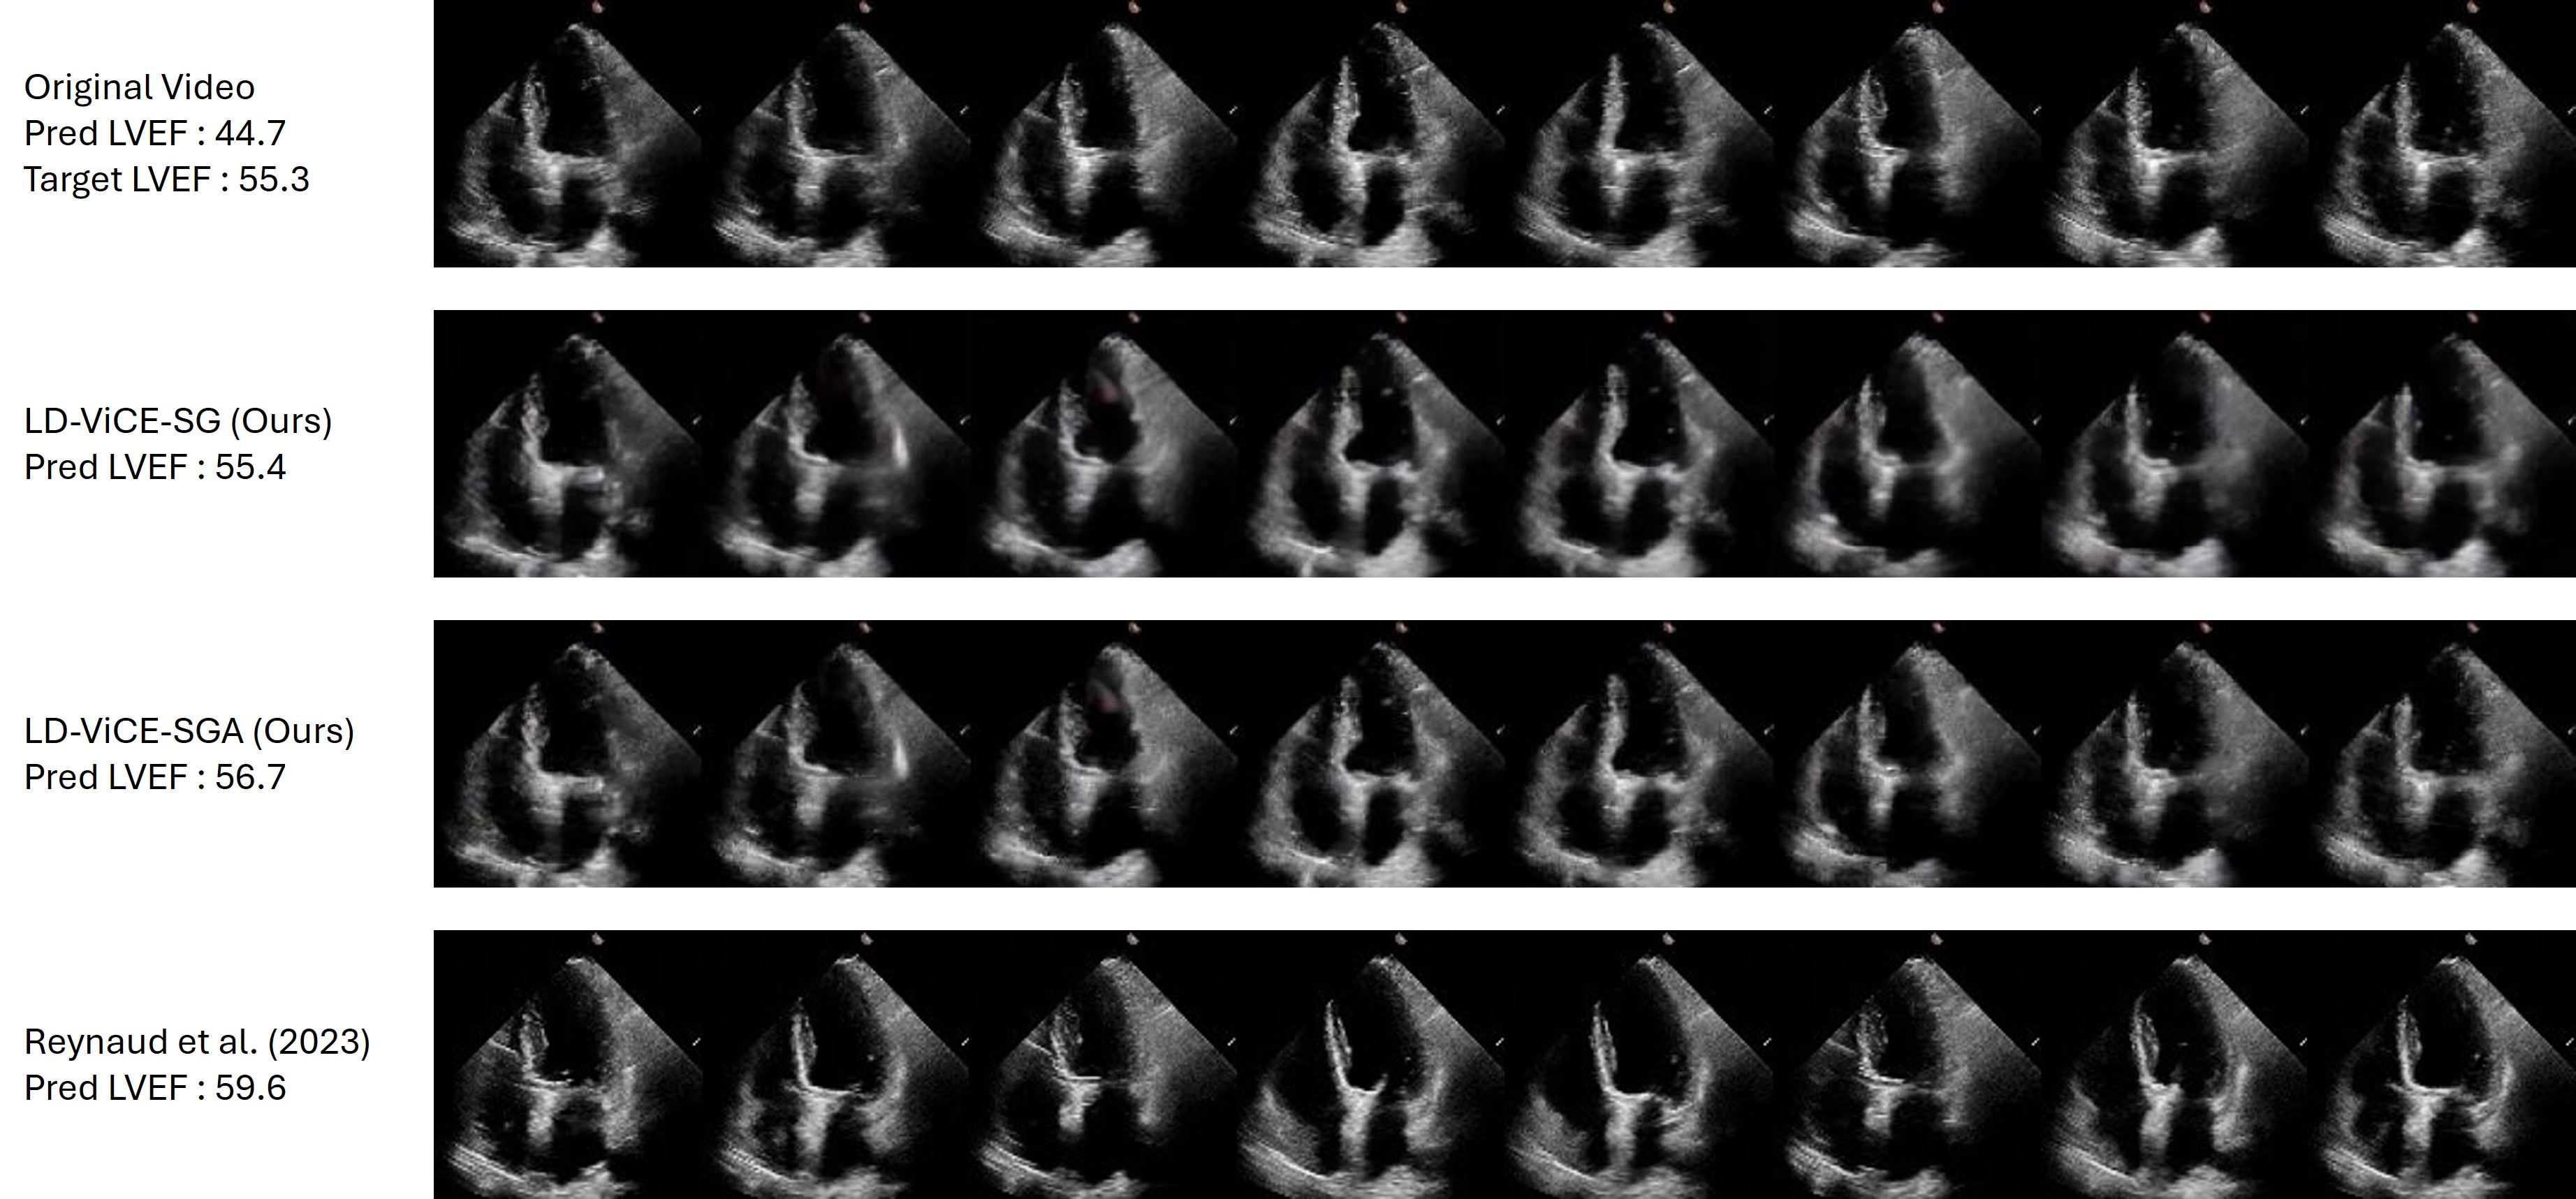

Refer to caption

Figure 3: Qualitative comparison of counterfactual explanations on the EchoNet-Dynamics dataset, demonstrating LD-ViCE’s improved alignment between counterfactual explanations and target regression values. The first row displays eight frames from the original video, while the following rows show counterfactuals generated using LD-ViCE-SG, LD-ViCE-SGA, and EchoDiffusion (Reynaud et al. 2023), respectively. The predicted and target LVEF values are given on the left.

Regression Results

Figure 3 compares counterfactuals from LD-ViCE variants and the baseline (Reynaud et al. 2023) on the EchoNet‑Dynamics dataset for LVEF prediction. The baseline (Reynaud et al. 2023) predicts an LVEF of 45.1, well above the target, likely reflecting its reliance on a single frame and target text without incorporating model feedback, which may limit temporal consistency. In contrast, LD-ViCE processes the whole video with gradient guidance, producing temporally coherent counterfactuals with tighter alignment to the target value. Among the variants, SG yields predictions closest to the target, whereas SGA achieves higher perceptual quality but deviates more from the target. This deviation may result from retaining subtle variations from the original video, including details that are not directly relevant to LVEF prediction.